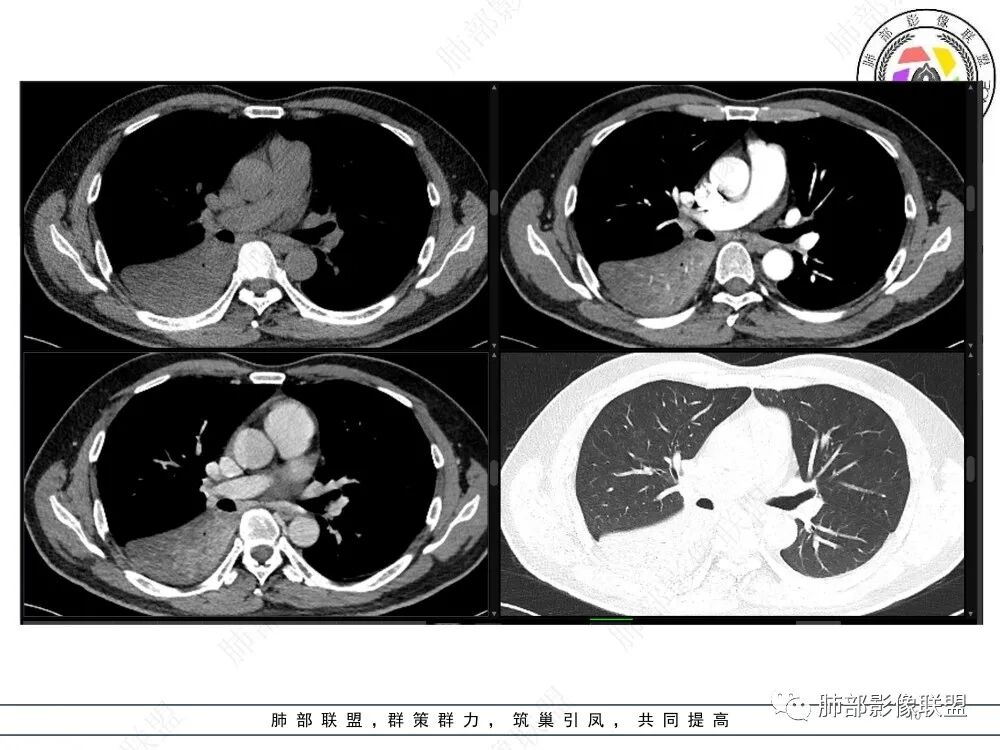

冠状位重建有钻缝的感觉

南边:

粘液腺不符合

粘液腺是外围朝内推移的

不应该近端腔内结节强化明显

我再发一些图

这是源头

这些如果单纯不张肯定强化明显